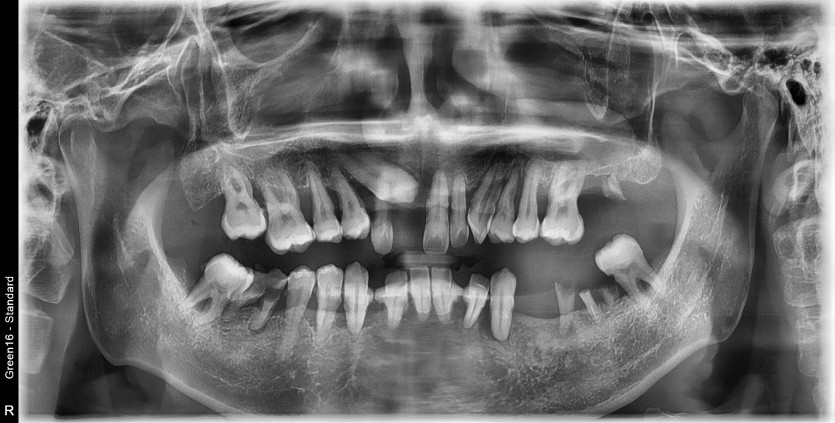

만 43세 전체 임플란트 증례

전체 임플란트 증례입니다.

18개의 임플란트로 완성하였습니다.